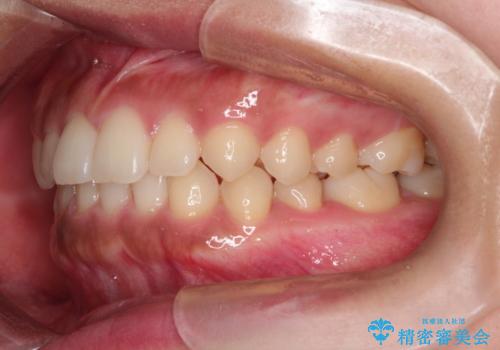

前歯の隙間を閉じたい。インビザラインによる治療

- 前歯の隙間を閉じたいと矯正カウンセリングに来られた患者様です。

マウスピース矯正(インビザライン)を行い短期間で治療が完了しました。